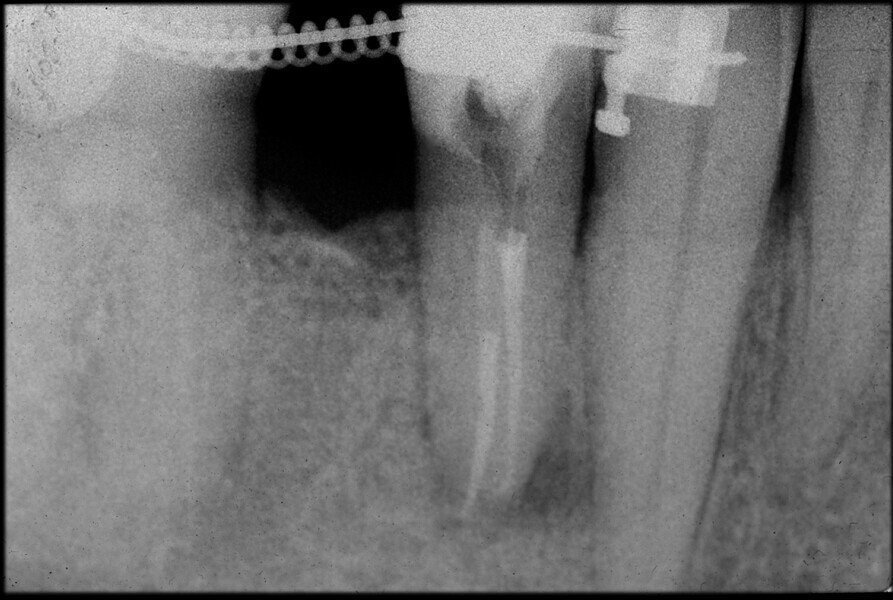

Use of 3D technology in the diagnosis and treatment of endodontic disease